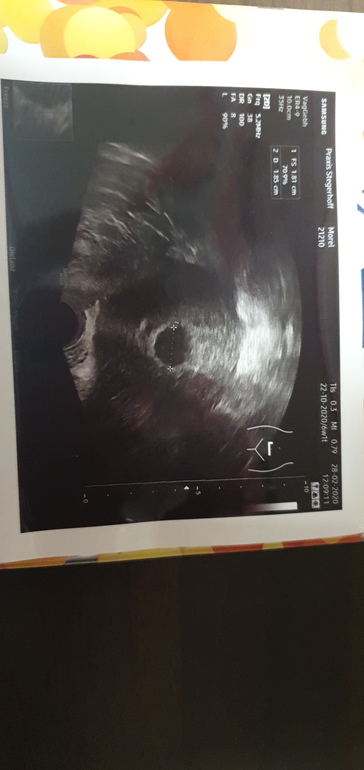

А можете мне посмотреть?

25.01.2021